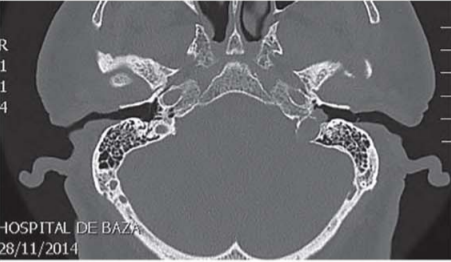

Se solicita un TAC de oído para valorar un posible granuloma intratimpanico, el cual informa de un glomus yugular (figura 1).